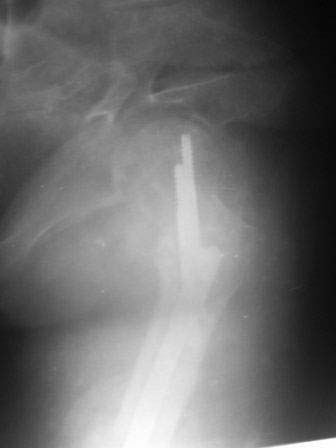

ЭОП унас нет, больной оперирован тогда, 35 дней назад, во время наркоза определена патологическая подвижность в вертельной обл, поэтому произведена

остеотомия с исправлением угла, антеградный БИОС ,универсальный стержень ChM. Рентген снимки свежие фас и аксиальная. Пациент ходит с двумя костылями, ногу частично нагружает, лежа выпрямленную ногу поднимает.